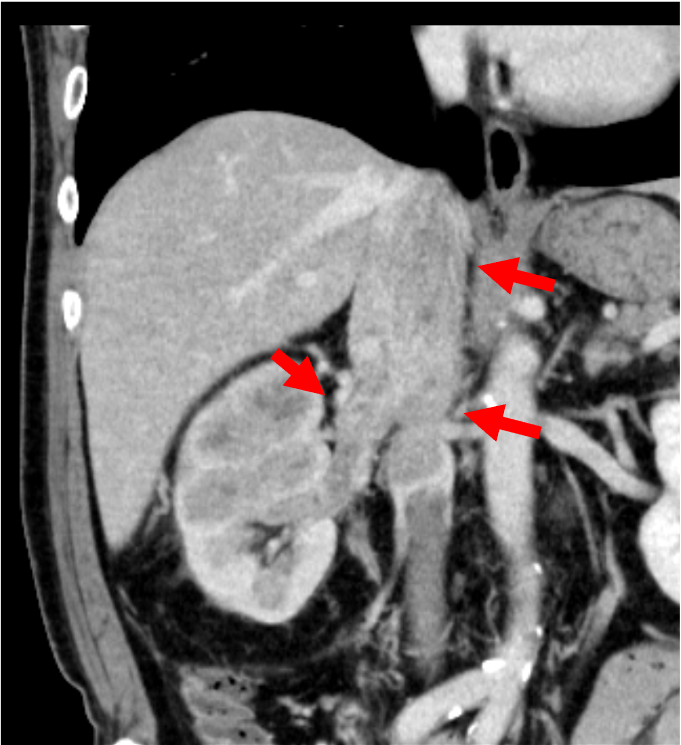

右腎には、実質を置換性に広がる早期濃染とwashoutを示す腫瘍を認め、腎細胞癌と考えられた。腫瘍は腎静脈を経て下大静脈に進展し横隔膜レベルに達していた。また左腎動脈には低造影域を認め、肺動脈腫瘍栓と考えられた。

腎腫瘍の診断において、ダイナミック造影CTはその組織型の推定に有用である。腎腫瘍の多くの割合を占める通常型(淡明細胞型)腎細胞癌は、早期相で周囲の腎皮質と同程度に濃染し(早期濃染)、後期相では周囲に比してやや低造影を示す(washout)ことが特徴である。さらに、腫瘍増大に伴い、本症例のように腎静脈や下大静脈へ進展が見られやすいのも特徴の一つと言えるだろう。また、本症例では腎動脈に塞栓を疑う低造影域を認めた。多くは血栓塞栓であり、その場合は原因となる下肢静脈血栓の有無を検索する必要がある。しかし、本症例では肺動脈内病変には斑な造影効果を認め、FDG-PET(非提示)では集積像を示した。静脈内進展を伴う腎腫瘍の存在と合わせて肺動脈腫瘍栓と診断した。肺動脈塞栓を認めた場合には、血栓以外の可能性についても一考することが大切である。